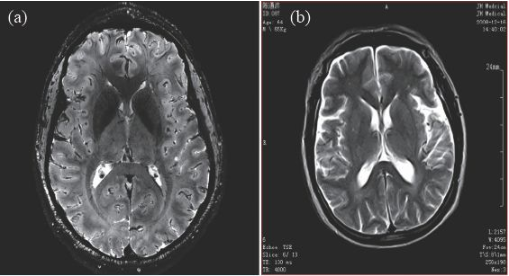

因此,磁共振成像技術目前的發(fā)展趨勢,是朝著更高磁場強度發(fā)展,以期獲得更高分辨率的圖像,并實現(xiàn)多核成像。圖6 顯示了磁場強度的高低對圖像分辨率的影像,(a)為7 T 磁場下的圖像,(b)為0.35 T磁場下的圖像,二者的圖像分辨率可見一斑。

圖6 T2 加權成像(a)7 T 下的成像,分辨率約0.3 mm;(b)0.35 T下的成像,分辨率約1 mm